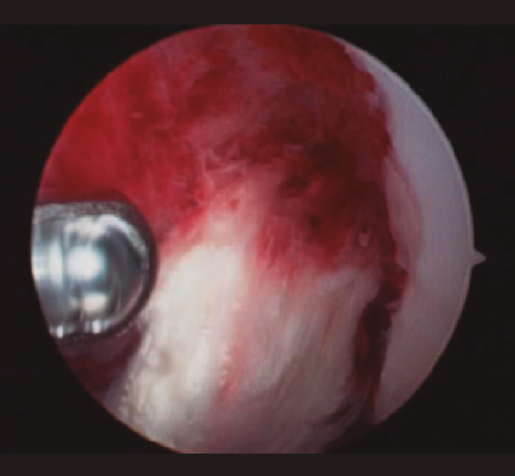

Figura 4. Imagen intraoperatoria artroscópica que muestra el aspecto de la plastia de LCA tras el desbridamiento del tejido sinovial.

También se sugiere eliminar la capa de fibrina que cubre la superficie del injerto y evaluar la integridad macroscópica del injerto, así como su tensión. No es necesario retirar la plastia en todos los casos, debiendo reservarse esta actuación para aquellos casos en los que se objetive un claro fracaso en su funcionalidad, aspecto séptico durante la artroscopia o persistencia de la infección pese al tratamiento correcto(4).